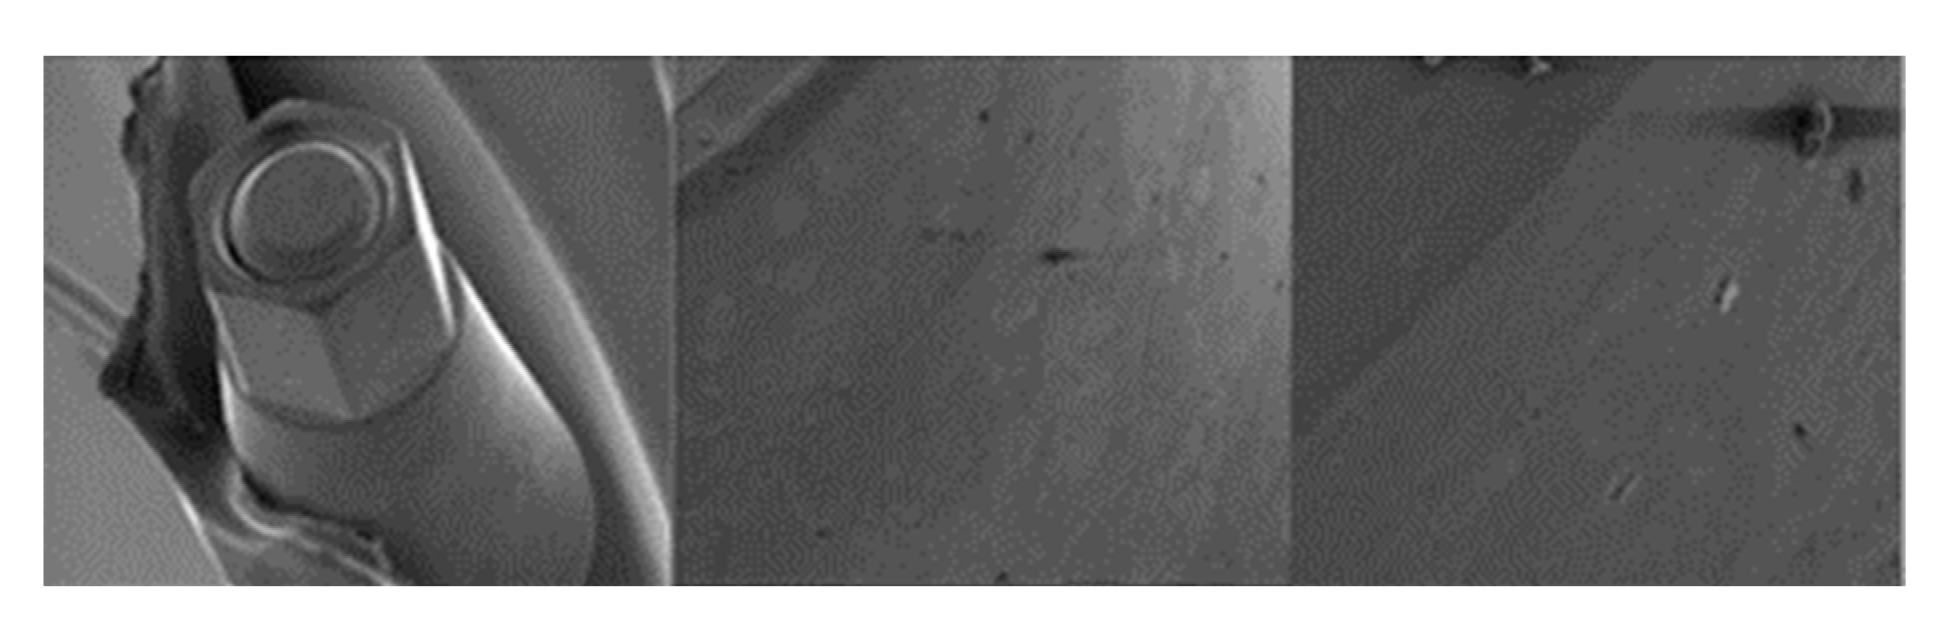

3.1.2. Essential Implants

3.1.4. Vega Implants

4.1. SEM Evaluation